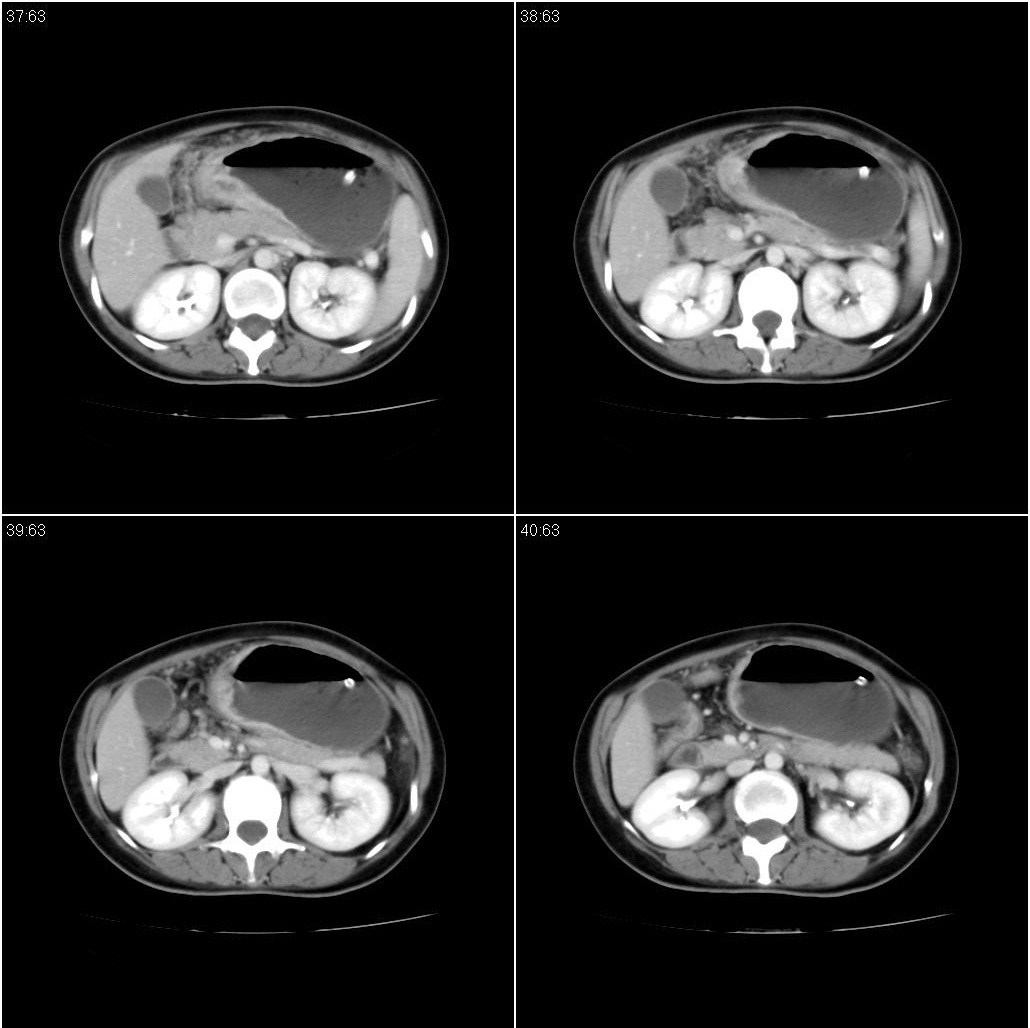

标题: CT21386:女性,33岁。4个月前因妊娠发现盆腔肿物。 [打印本页]

标题: CT21386:女性,33岁。4个月前因妊娠发现盆腔肿物。

女性,33岁。4个月前因妊娠发现盆腔肿物。ca-125: 1100

胃幽门部癌伴小弯侧和腹腔淋巴结转移,胃内有胃管。

胃窦贲门胃小弯好像都厚啊 ,胃窦处比较明显,而且胃腔扩张明显,考虑胃癌伴梗阻。

支持;胃癌【浸润】幽门梗阻.胰头、胆囊及肝左叶受侵,副脾.

考虑胃窦占位并肝门部淋巴结转移

考虑胃窦部胃癌伴小弯侧和腹腔淋巴结转移。